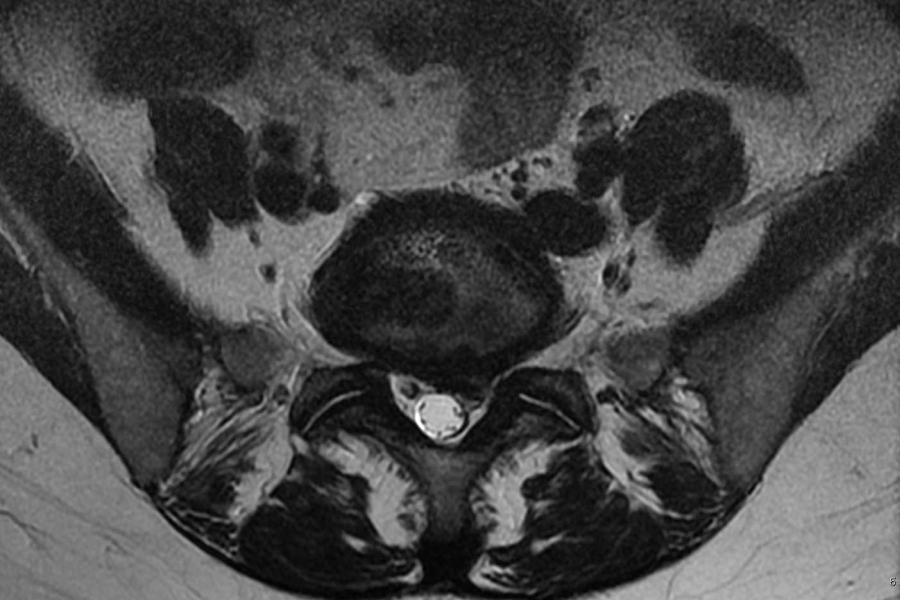

Laser Disc Decompression Surgery . Percutaneous laser disc decompression is a minimally invasive treatment, for lumbar disc herniation and might serve as an. The main objective of surgical treatment of a disc prolapse, protrusion, or extrusion is the relief of nerve root compression by removing the herniated. The main objective of surgical treatment of a disc prolapse, protrusion, or extrusion is the relief of nerve root compression by removing the herniated. The aim of percutaneous intradiscal laser ablation (also commonly referred to in the literature as percutaneous laser disc.